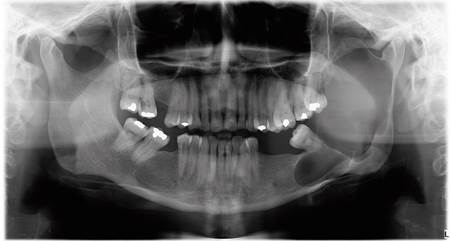

Paciente de sexo mujer, 42 años de edad, con antecedentes de hipotiroidismo en tratamiento, acude al Servicio de Cirugía Oral y Maxilofacial del Hospital San Juan de Dios, en Santiago de Chile, por aumento de volumen hemifacial izquierdo de 6 meses de evolución. Al examen clínico se observó un aumento de volumen de la región parotídea y submandibular izquierda (figura 1), desdentamiento parcial bimaxilar, abombamiento tablas óseas mandibulares y movilidad de tercer molar inferior izquierdo (diente 3.8) (figura 2). La radiografía panorámica reveló extensa lesión en zona posterior del cuerpo y en casi la totalidad de la rama mandibular izquierda, de características quísticas y expansivas, sugerentes de quiste odontogénico (figura 3). En la tomografía axial computarizada (TAC) se observó una lesión de aspecto quístico en la región mandibular izquierda, desde cuello condilar hasta cuerpo mandibular izquierdo, con expansión de corticales óseas vestibular y lingual (figura 4).